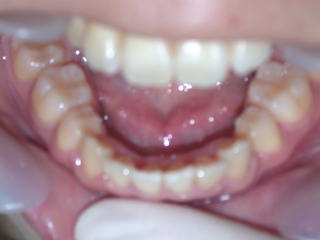

2022年7月25日初診、20代女性の叢生症例 (新潟県長岡市要町 要町歯科 歯科矯正 歯列矯正)

2024年5月15日装置除去

術前術後

2022年7月→2024年5月(2年弱でした。これから保定期間に入ります。)